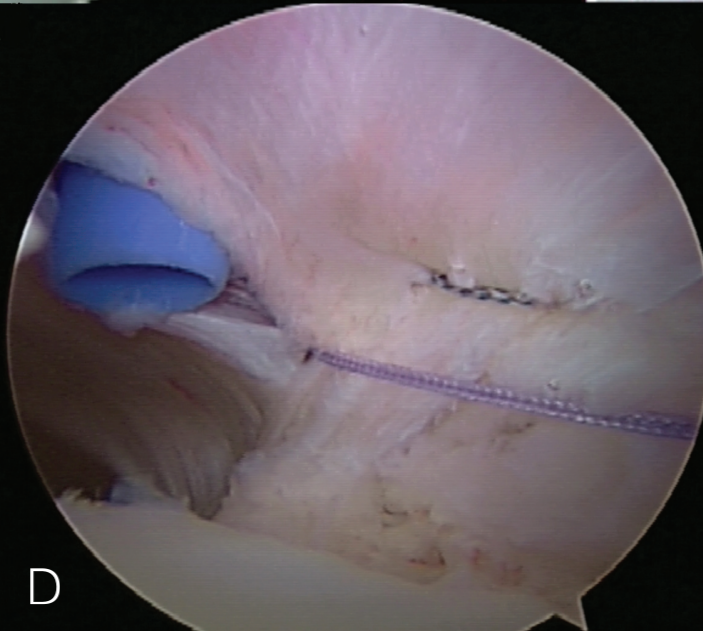

上盂唇修复

创建前方和后方入路时,与关节盂面成恰当角度,以便锚钉的置入。 高位和外侧放置前方入路可以有效地进行单纯上盂唇的修复。该入路位于肩袖间隙的高位和外侧,用腰椎穿刺针进行定位。非刚性套管有助于在肱二头肌腱附着部后方置入锚钉。 可用于 SLAP 修复的辅助入路包括 Wilmington 入路(肩峰后外侧角前方、外侧各 1 cm 处)或 Neviaser 入路(锁骨、肩峰、肩胛冈组成的三角形内,肩峰内侧 1 cm 处)。